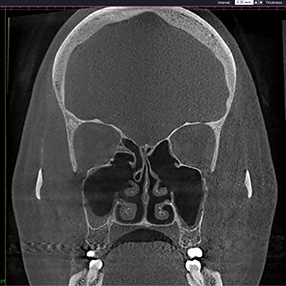

※ 축농증 수술 후 생길 수 있는 부작용으로는 출혈, 감염, 염증이 있을 수 있습니다.

본 사진은 의료기관에서 진료를 본 환자이고, 전후 사진 인물이 동일인이며,동일조건에서 촬영이 되었습니다.